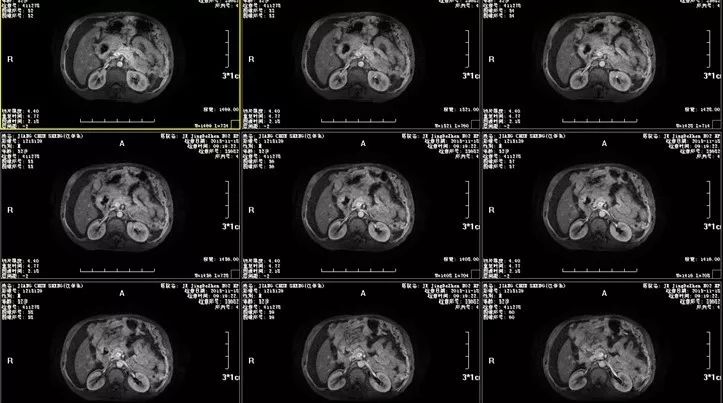

腹水检查仍不能明确病因,接下来行腹部MRI检查,结果示:1.十二指肠球部占位,考虑肿瘤性病变,建议MR增强扫描;2.肝尾叶异常信号影,建议进一步检查;3.大量腹水。

图二 腹部MRI检查图